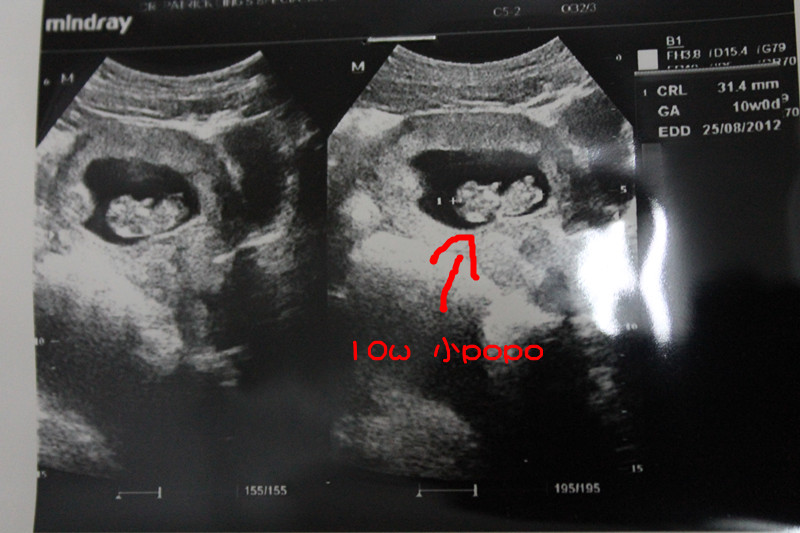

2012/01/28

我自己又去看了sibu的医生~dr。Lim~

看到Ta在动~

小小手手脚脚都看到了~心跳也听了~

小popo~

26/08/2012就可以看到把拔麻妈咯~

30/01/2012

第一次产检~

baby很好~把拔也看到小popo了~